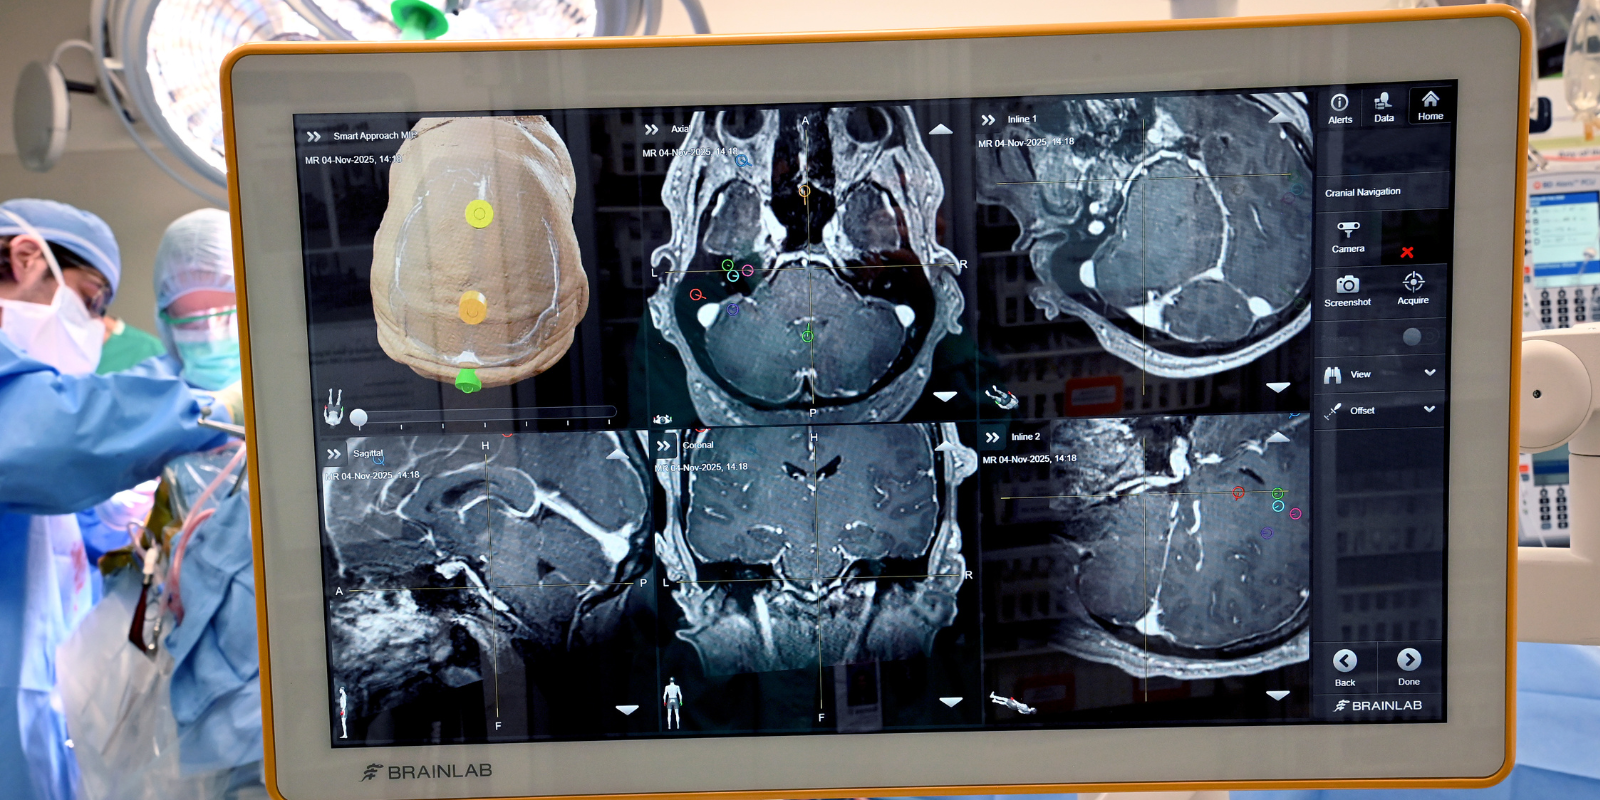

A series of images of the brain are on a display, from a variety of angles. In the lefthand corner past the display, surgery in the operating room is underway.

Neurosurgery experts with the University of Colorado Anschutz performed Colorado’s first implanted brain‑computer interface (BCI) surgery at UCHealth University of Colorado Hospital, marking a significant advance for patients with neurological injury or disease. Commonly known as BCIs, the implanted technology can restore lost motor and sensory function by translating brain signals into actions for people with paralysis or neurodegenerative movement disorders.